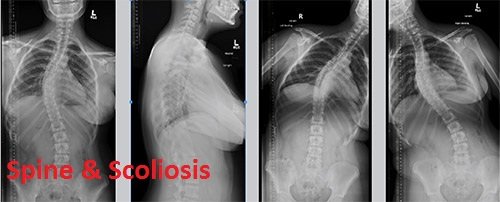

If you look at someone’s back, you’ll see that the spine runs straight down the middle. When a person has scoliosis, their backbone curves to the side.

The angle of the curve may be small, large or somewhere in between. But anything that measures more than 10 degrees is considered scoliosis. Doctors may use the letters “C” and “S” to describe the curve of the backbone.

You probably don’t look directly at too many spines, but what you might notice about someone with scoliosis is the way they stand. They may lean a little or have shoulders or hips that look uneven.